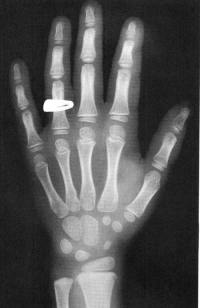

Sexo Masculino

3 meses

idade óssea - 3m